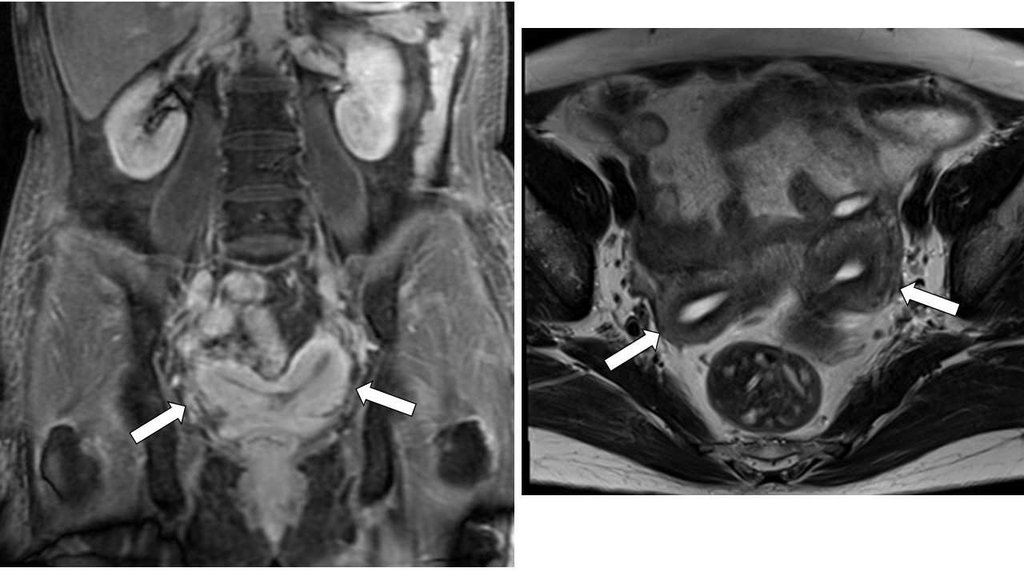

【108-2 醫學(六) 第74題】

一位年輕女性磁振造影檢查呈現如圖,箭號所指之敘述何者最正確?